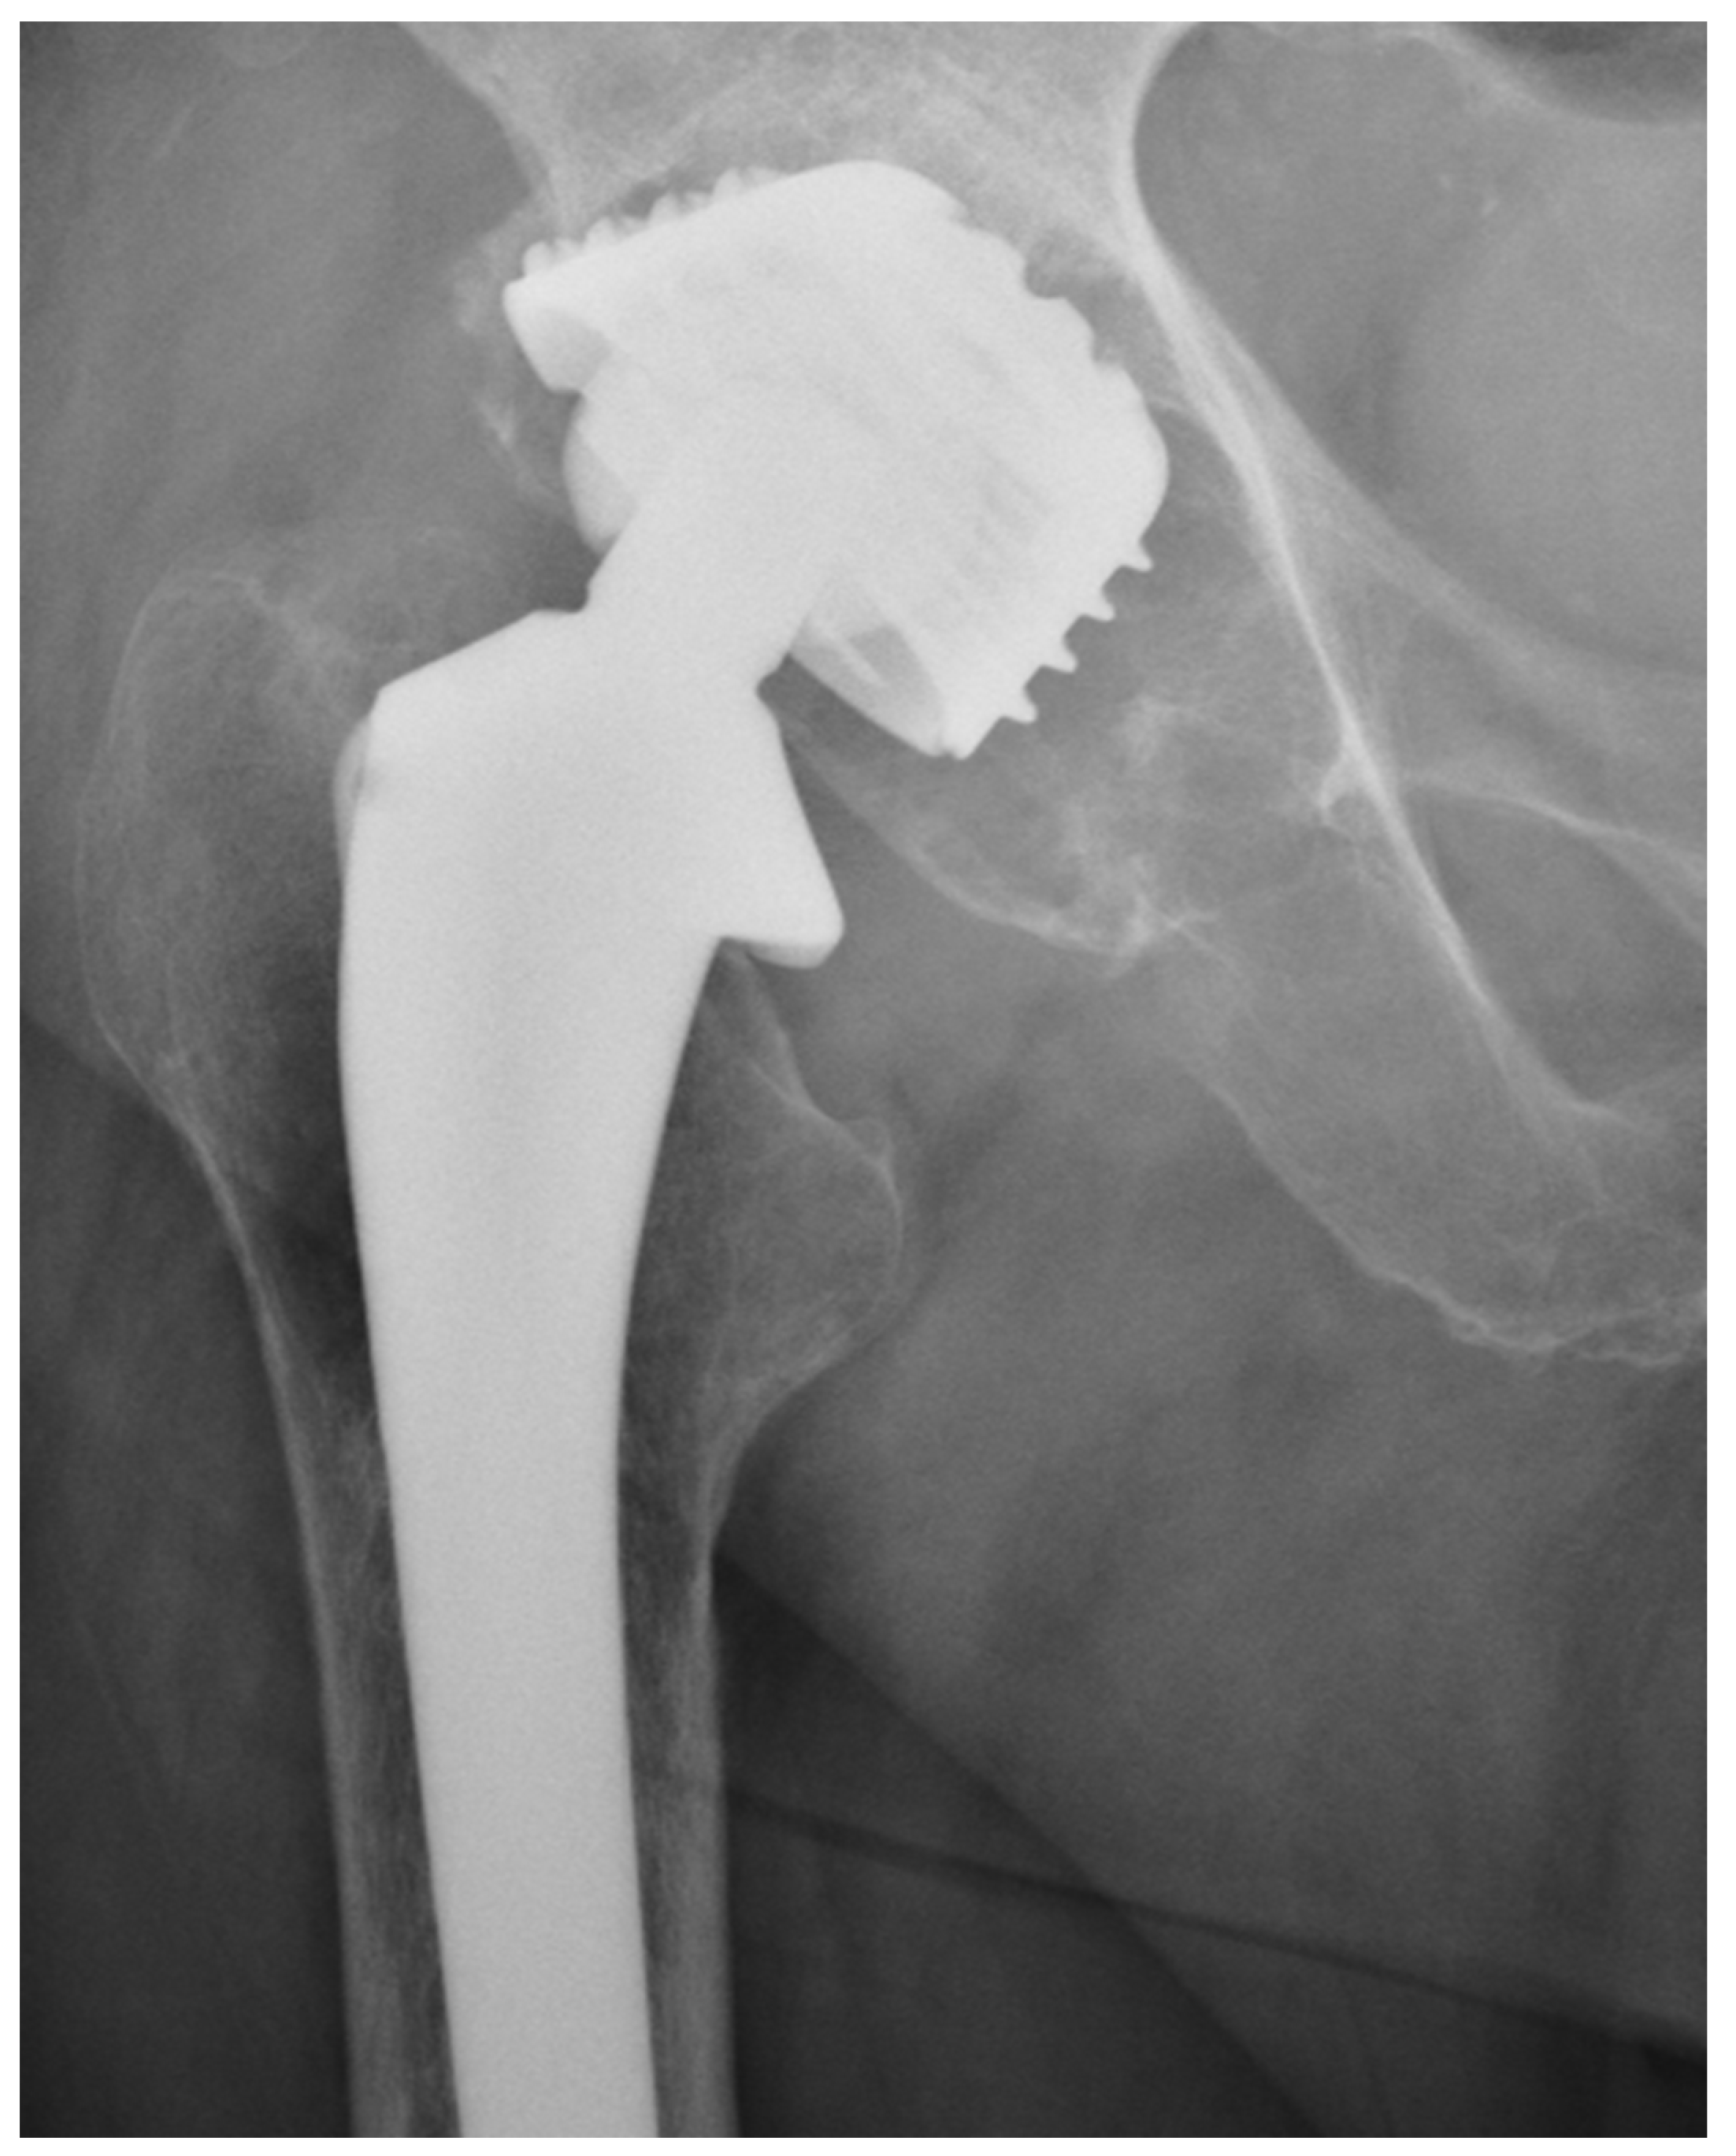

We observed a positive correlation between the increase in the mean oxidation index (OI) of the bearing surface of the inlays and the extent of periacetabular osteolysis classified according to the Paprosky scale (R = 0.44; p = 0.011). The most commonly revised types were 3A and 2B: 12 out of 33 samples (36.36%) were classified as type 3A, and 7 out of 33 samples were classified as type 2B (21.21%) according to Table 2. Mean oxidation index values for each type are, respectively, presented in Table 3. Figure 1 illustrates the differences in oxidative indices between the control sample and selected samples from groups 1 and 3B. Attention should be paid to the difference in the spectrum range of 1685–1745 cm−1. Representative X-ray images of patients depicting the extent of osteolysis based on the Paprosky scale can be seen in Figure 2, Figure 3 and Figure 4.

Figure 2. Periacetabular osteolysis classified as Paprosky 1.

Figure 3. Periacetabular osteolysis classified as Paprosky 2B.